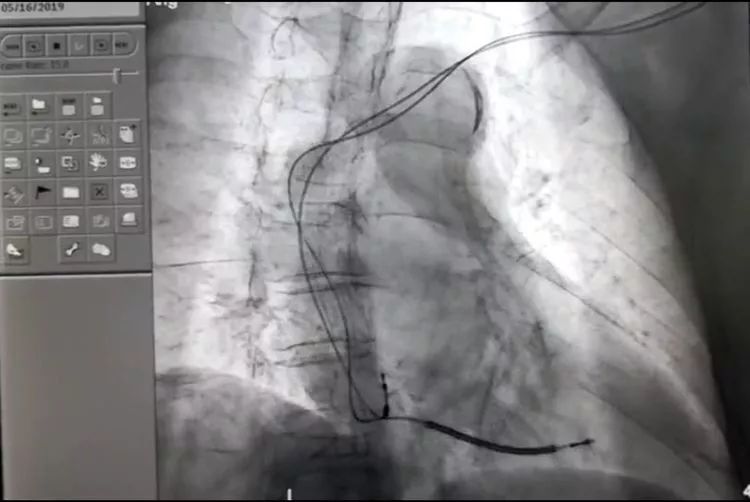

双腔ICD植入术:手术中